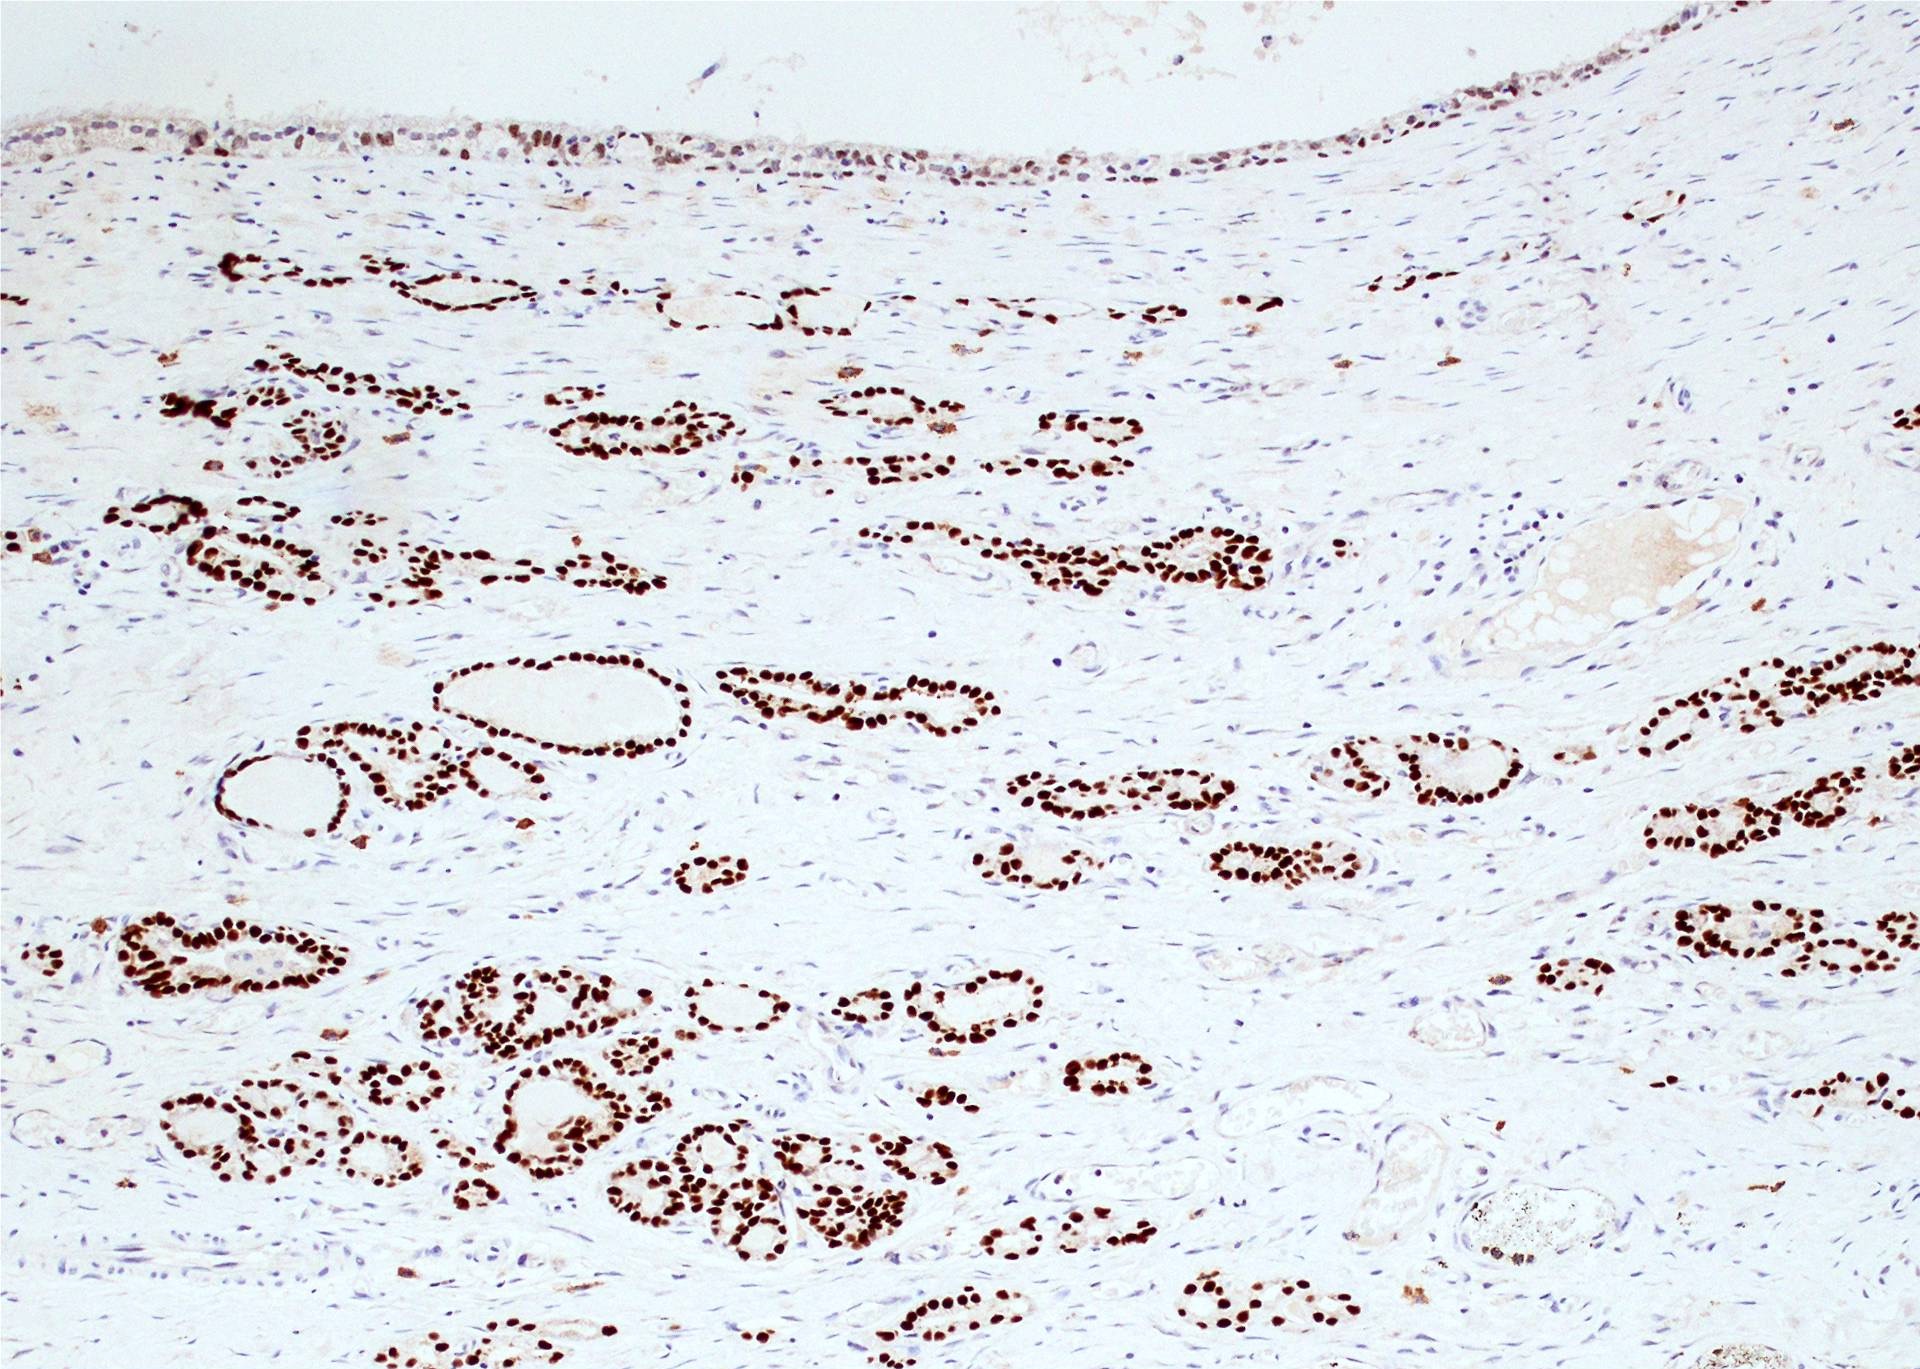

Microscopic (histologic) description

- Type of epithelial lining varies by site, and combinations of the types below can be seen in a single cyst (Head Neck Pathol 2013;7:50):

- Ciliated pseudostratified columnar (respiratory) epithelium in lower neck, perhaps due to its close proximity to upper respiratory tract

- Nonkeratinizing squamous epithelium in higher neck (near tongue and foramen cecum), also can be of metaplastic origin in inflammatory settings

- Stratified cuboidal epithelium at level of hyoid bone

- Very often the cyst is denuded of epithelium, at least focally, which reflects epithelial damage by inflammation

- Thyroid follicles in the cyst / duct wall:

- Found in 30% - 60%, with higher yield on serial sections

- More common in infra- versus suprahyoid remnants, on the right paramedian side (Ann Otol Rhinol Laryngol 2000;109:1135)

- Seen in small irregular groups

- Thyroid epithelium may be normal or rarely hyperplastic or neoplastic

- Thyroid tissue often hidden by inflammation (Laryngoscope 2001;111:1002)

- Absence of thyroid tissue does not exclude the diagnosis of TGD cyst

- Mucous salivary-type glands can be found in the cyst wall, frequently in lingual and suprahyoid locations (Ann Otol Rhinol Laryngol 1996;105:996)

Microscopic (histologic) images

Contributed by Andrey Bychkov, M.D., Ph.D., Mark R. Wick, M.D. and AFIP